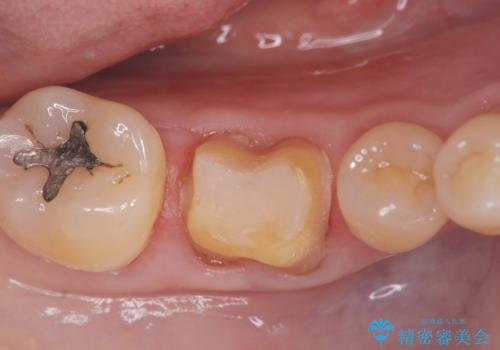

- 「銀歯を白くしたい」を主訴に来院された患者様です。銀歯を外し虫歯を除去後、オールセラミッククラウンで治療を行いました。

銀歯を外して内部の虫歯を丁寧に除去した後、オールセラミッククラウンにて修復を行いました。審美性と機能性の両面で改善が得られ、患者様にもご満足いただきました。